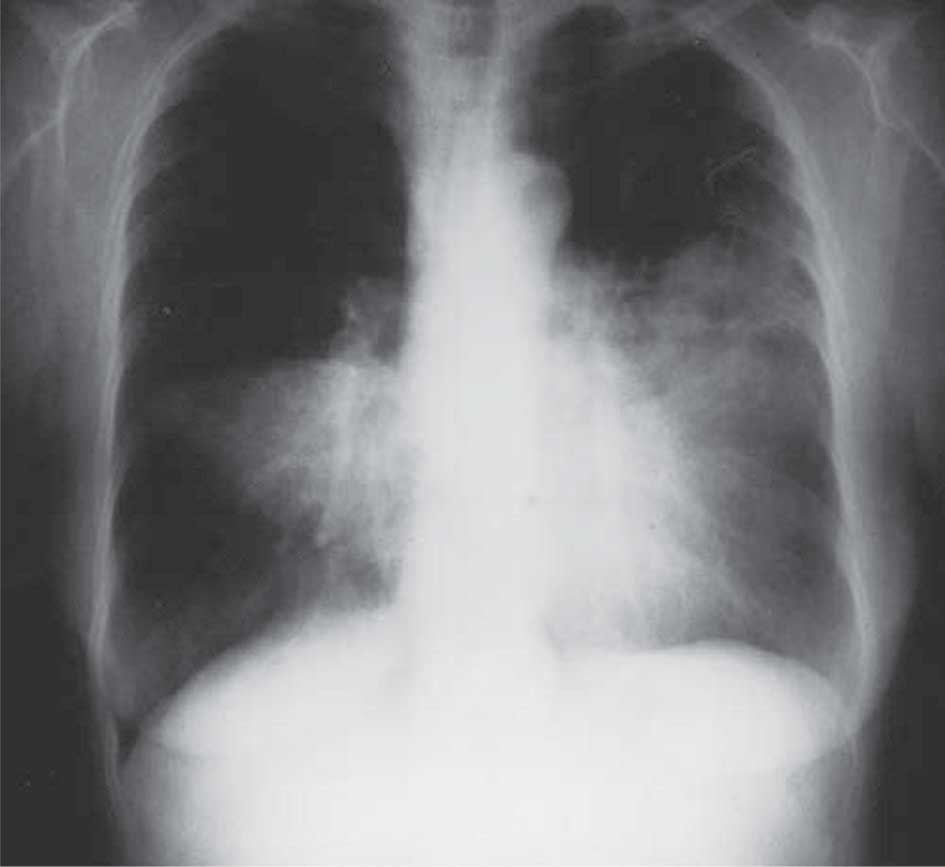

1- التصوير الشعاعي: ليس هناك مظهر مرضي شعاعي وصفي للسارس وتختلف الموجودات في صورة الصدر البسيطة من حالة إلى أخرى، فقد تكون الصورة في بدء المرض طبيعية، ولكن يغلب أن تظهر مع تطوره ارتشاحات بقعية في أقسام عديدة من الرئتين (الشكل2)، وقد يظهر تصوير الصدر المقطعي المحوسب شذوذات في المتن الرئوي parenchyma حتى في المرضى الذين بدت صورة الصدر البسيطة لديهم طبيعية (الشكل 3)، وتشاهد في الحالات المتقدمة كيسات صغيرة (بقطر > 1سم)، كما سجلت حالات من الريح الصدرية والريح المنصفية.

الشكل (2) ارتشاحات متنية في التصوير الطبقي المحوري | الشكل (3) صورة الصدر البسيطة |